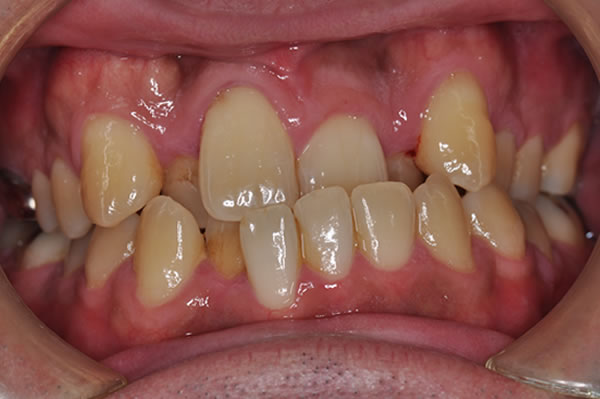

反対咬合症例

治療前(初診)